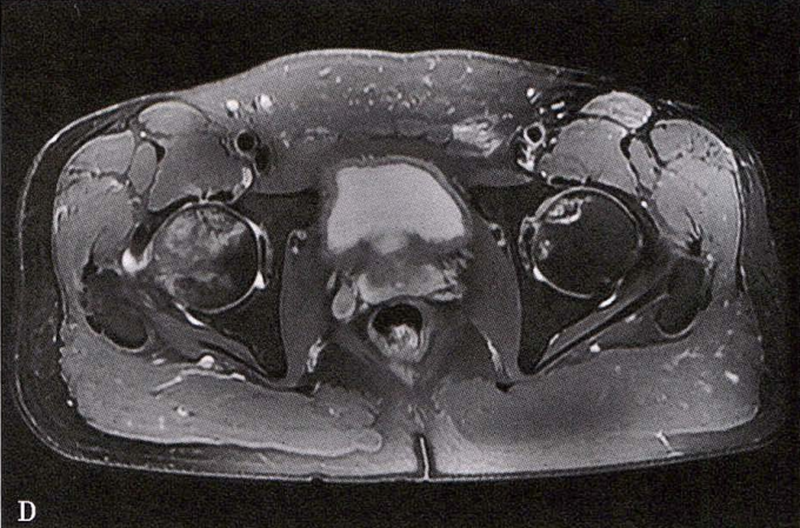

B.男性,31岁,双侧股骨头坏死,双侧均为Ⅲ期。X线片示双侧股骨头密度不均、股骨头稍变扁(B1)。MRI(T1加权像)示股骨头内多发不规则信号带(B2),股骨头内凸向大转子的双线征(白色箭)和软骨下骨骨折(白色三角)。